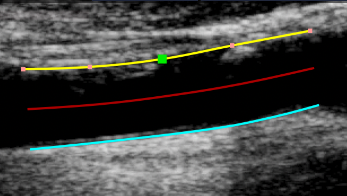

Tracing a plaque

• Click the Trace the Plaques images/download/thumbnails/388694064/cvs_plaques_button-version-1-modificationdate-1761815630095-api-v2.png button in the Setup panel.

• Hover on the border where the plaque is attached and click to start tracing.

• Move the mouse and click to add points to the plaque.

• Right click to end the tracing of the plaque.

Editing a plaque

• Hover on the plaque to be modified.

• Click and drag one of the points of the plaque.